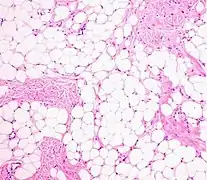

- Histopathology of a lipoma: The mass is composed of lobules of mature white adipose tissue divided by fibrous septa containing thin-walled capillary-sized vessels.[25] H&E stain.